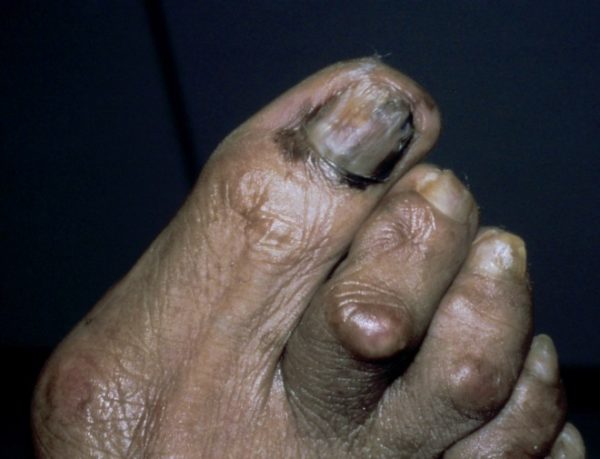

When a dark spot appeared under his toenail, Marley attributed it to a soccer injury. Eventually, he was diagnosed with a rare, aggressive type of skin cancer called acral lentiginous melanoma (ALM). ALM comes from “acral,” an anatomical term for the peripheral parts of the body, and “lentiginous,” for freckled appearance.

Acral lentiginous melanoma example (not a photo of Bob Marley). Photo credit: Hugh Gloster, MD

Most melanomas are caused by exposure to ultraviolet (UV) radiation from the sun or from tanning beds. But ALM, which develops on hairless skin such as under nails, on the soles of the feet or palms of the hands, is more likely caused by genetic factors. While ALM is rare overall, it is the most common form of melanoma found in people of color.